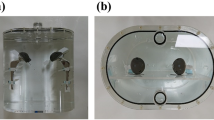

A human left femur was obtained from an anatomical lab. The distal third was sawn away to fit the remainder into a 42 by 24 by 15 cm polypropylene container. A neck osteotomy was performed, and the marrow cavity was reamed to fit the femoral stem of a prosthesis composed of a chrome-cobalt alloy (Fig. 1). The femur was covered in cellophane tape to ensure structural integrity. The titanium acetabular prosthesis component was taped over the ceramic joint in its correct anatomical position using Mefix surgical tape. 1.5 cc Eppendorf tubes (Eppendorf, Aarschot, Belgium) were filled with a solution of 2.975 MBq in 0.2 l water (or 14.88 MBq/l), so as to obtain an approximate target to background ratio of 10:1. They were fixed to the assembly by surgical tape in five positions: at the medial and lateral border of the cup, at the superolateral and inferomedial borders of the prosthesis neck and at the greater trochanter (Fig. 2). These locations were inspired by the Reinartz patterns of prosthetic infection [16, 17].The whole assembly was immersed in an aqueous solution of 7.5 MBq of 18F-FDG in slightly more than 5 L in the polypropylene container (the exact volume was unknown because some water had to be added to ensure complete immersion of the femur). A cylindrical acrylic uniformity phantom of 20 cm diameter and 18 cm height was positioned in front of the plastic container. It was filled with a solution of 8.31 MBq in 5.701 l, so as to simulate abdominal/pelvic background. Figure 3 shows the experimental setup.

Next, the prosthesis was extracted from the femur, the original femur head was taped to the diaphysis and the Eppendorf tubes were each taped to the femur in similar positions as for the first experiment, although we had to take into account the larger dimension of the anatomical neck as opposed to the prosthesis neck and the smaller surface area of the femoral head. To keep the femur immersed, it was taped to the bottom of the container. An acquisition with identical parameters as the first one was subsequently performed.